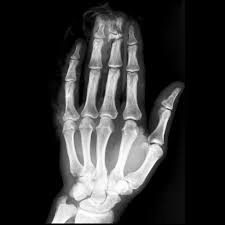

Middle phalanx fracture treatment. Injuries can occur at the proximal middle or distal phalanx. 1 Holding your middle and big knuckle straight with your other hand bend the top joint as far down as is comfortable until you feel a gentle stretch. Phalanx fractures are common hand injuries that involve the proximal middle or distal phalanx.

Bilisation usually obtain full function. Undisplaced metaphyseal and articular fractures may also be treated nonoperatively. Most phalangeal fractures are treated with a splint but unstable fractures may require surgical treatment to prevent complications such as stiffness and malunion.

Articular fractures of the digits. Nondisplaced phalanx fractures are managed with splint immobilization. Operative treatment of intra-articular fractures of the dorsal aspect of the distal phalanx of digits. Injuries can occur at the proximal middle or distal phalanx. Treatment involves immobilization or surgical fixation depending on location severity and alignment of injury. Diagnosis can be confirmed with orthogonal radiographs of the involve digit. Middle phalanx base fractures come in several varieties. 1 Holding your middle and big knuckle straight with your other hand bend the top joint as far down as is comfortable until you feel a gentle stretch. A proximal-third fracture usually angulates.